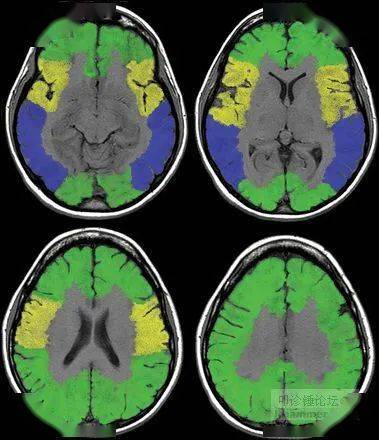

脑mri常用解剖

头颅mr高清解剖(必点收藏)